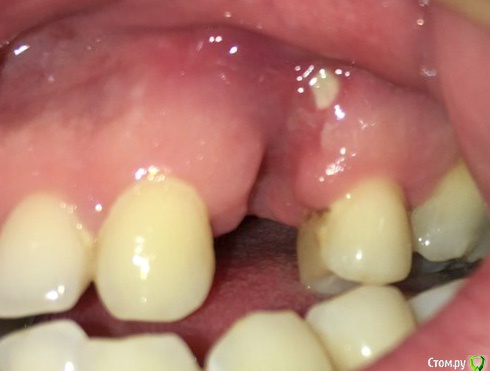

aleksei_sataev Опубликовано 3 декабря, 2017 Автор Поделиться Опубликовано 3 декабря, 2017 (изменено) Думаю, Вы на правильном пути.По моему пошел процесс заживления? https://cloud.mail.ru/public/6mVV/He7N5QarF боли нет, температуры тоже. К пластике после заживления конечно готов. Доктор спасибо, что уделяете своё время моей проблеме.. Изменено 3 декабря, 2017 пользователем aleksei_sataev Ссылка на комментарий

Irouil Опубликовано 4 декабря, 2017 Поделиться Опубликовано 4 декабря, 2017 Мало что видно на фото. Процесс заживления пошел ещё на предыдущем. Вам сейчас кроме как ждать полного заживления десны ничего особо не остаётся. Ссылка на комментарий

колесников Опубликовано 18 января, 2018 Поделиться Опубликовано 18 января, 2018 Все плохо Ссылка на комментарий

aleksei_sataev Опубликовано 18 января, 2018 Автор Поделиться Опубликовано 18 января, 2018 Все плохо Вроде затягивается. Ссылка на комментарий

aleksei_sataev Опубликовано 18 января, 2018 Автор Поделиться Опубликовано 18 января, 2018 с вероятностью 99 из 100 костная пластика потребуется. Мягкотканная 100 из 100. Доктор, а Вы, как считаете? Чуть лучше стало? Ссылка на комментарий

Irouil Опубликовано 1 февраля, 2018 Поделиться Опубликовано 1 февраля, 2018 Доктор, а Вы, как считаете? Чуть лучше стало? Мои прогнозы не изменились и до того как Вы сделаете КТ не изменятся. Но трагедии нет, все решаемо. 1 Ссылка на комментарий